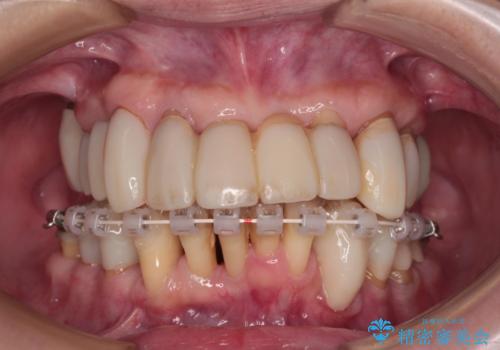

歯周病でグラグラの歯 矯正治療と歯周外科を併用した総合歯科治療

- 矯正装置

- 審美装置

診察を行ったところ、重度歯周病の状態の上に上下の歯列が著しい叢生という状態でした。